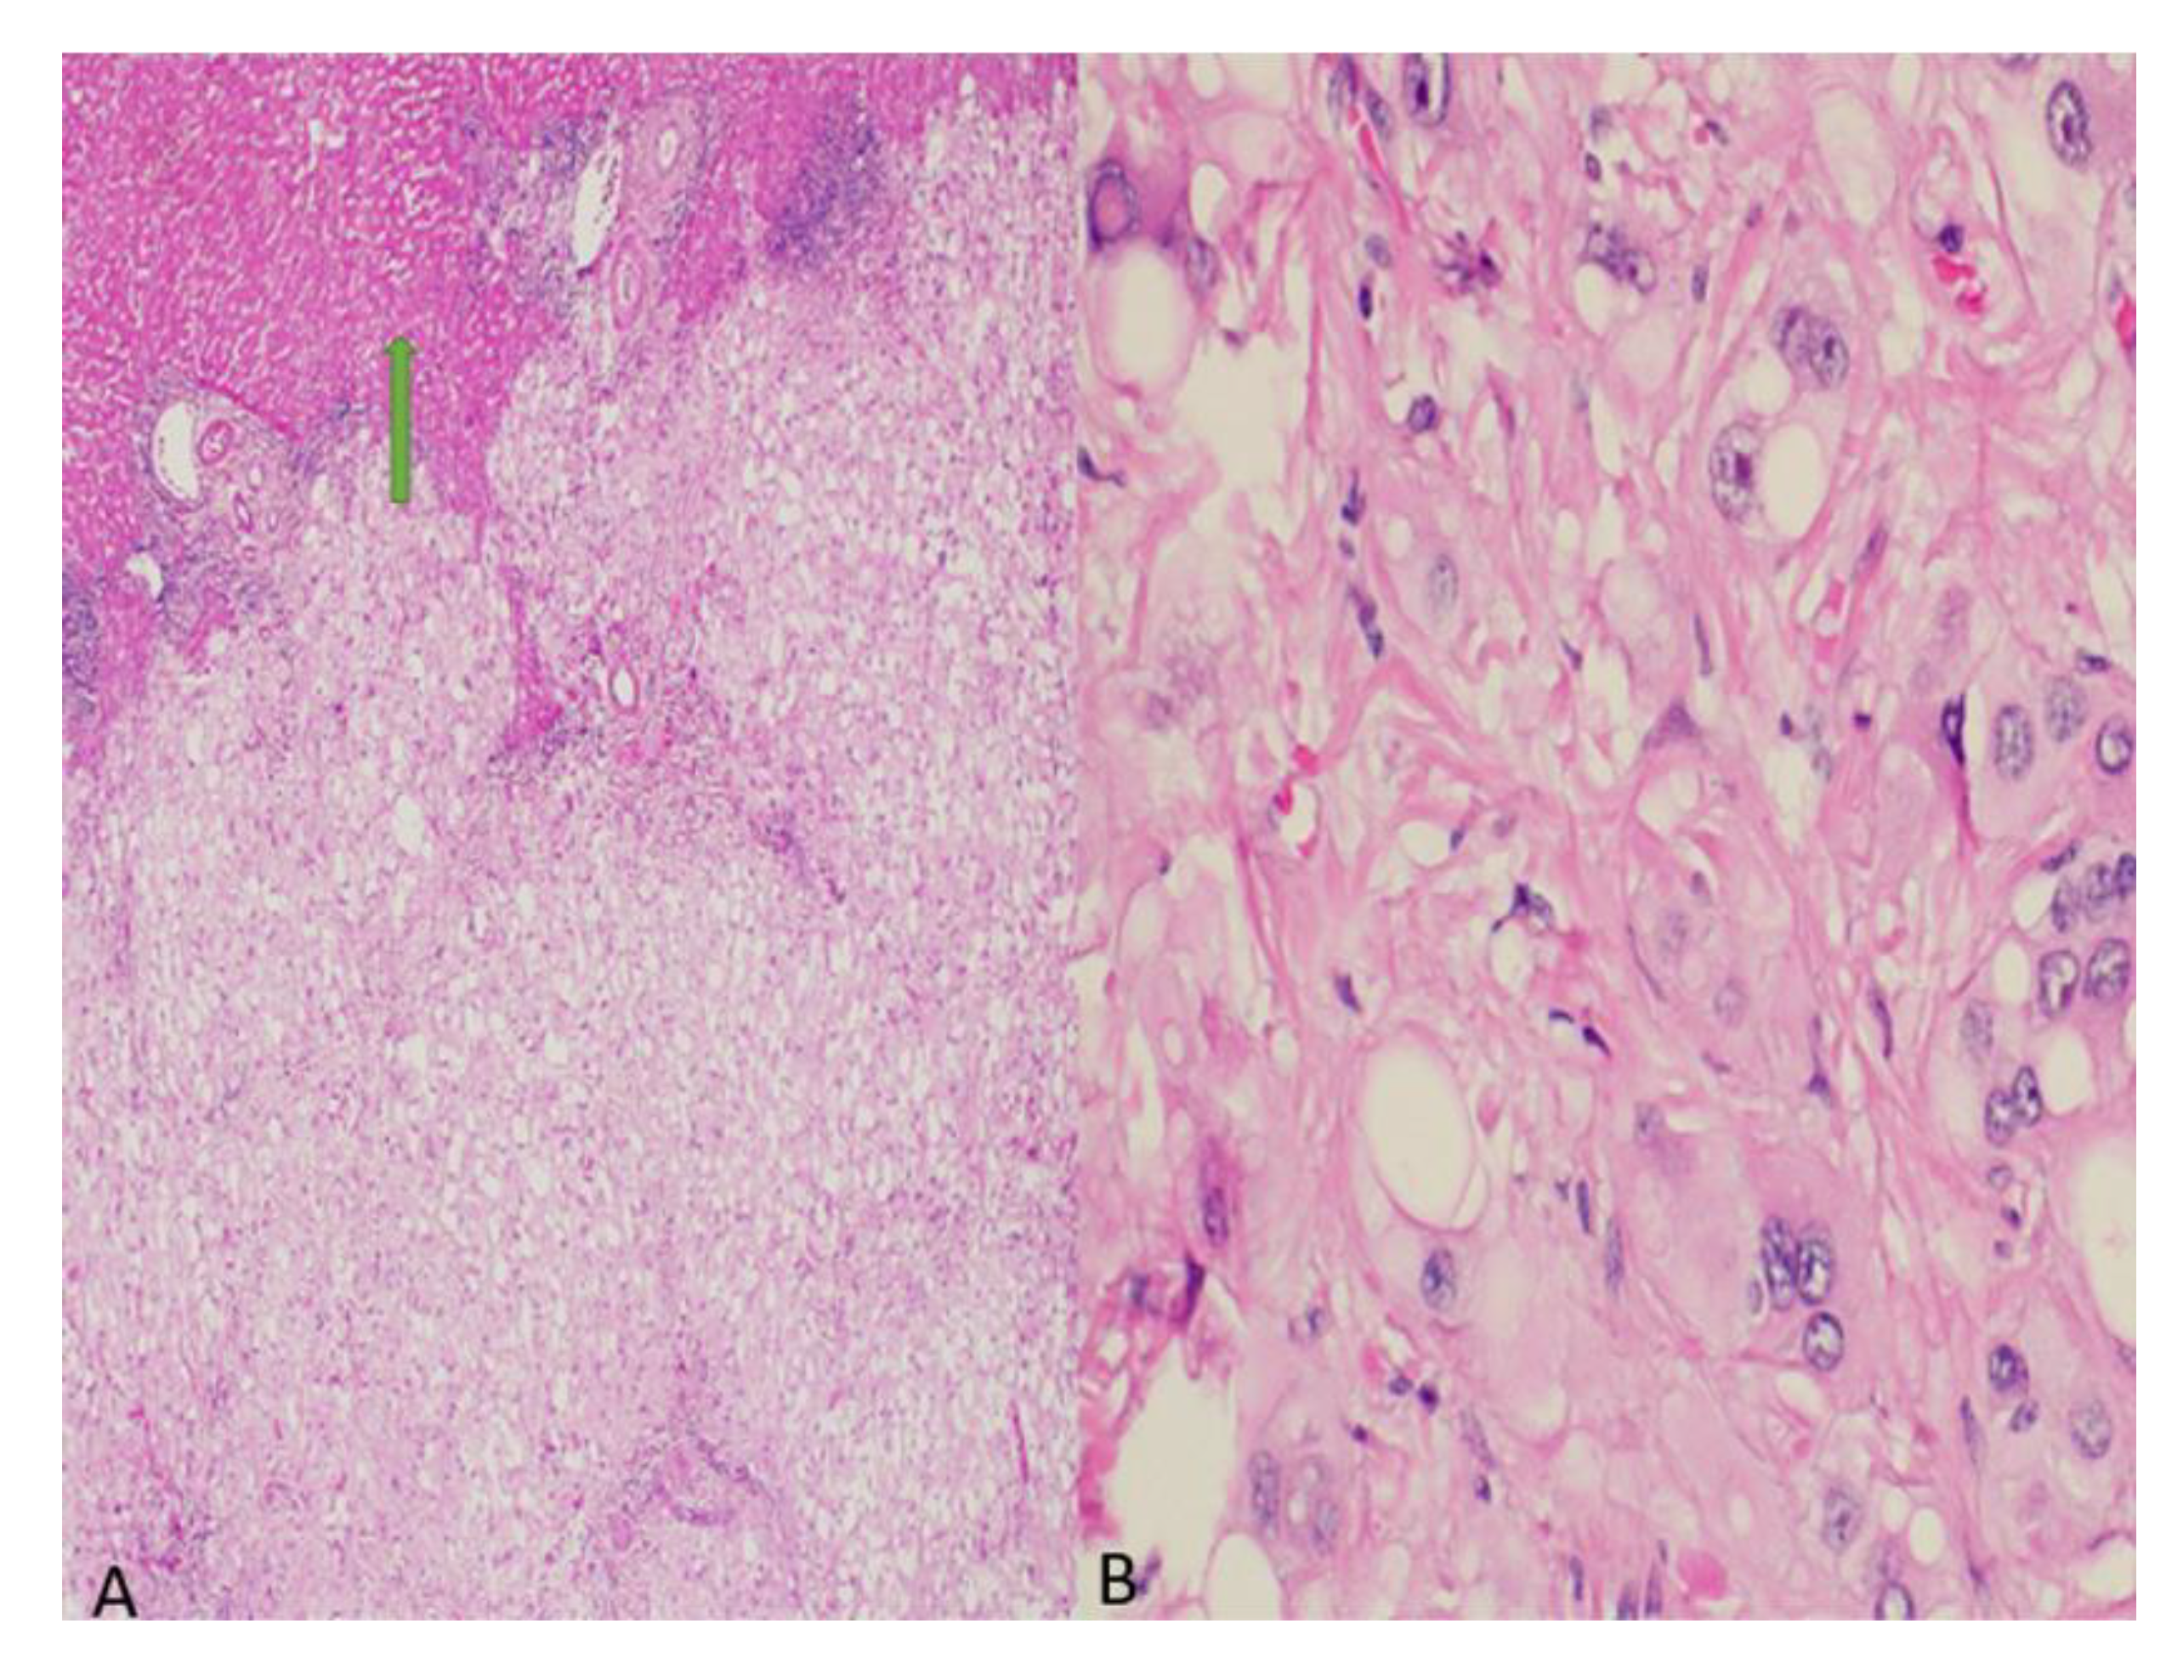

2. Case Presentation